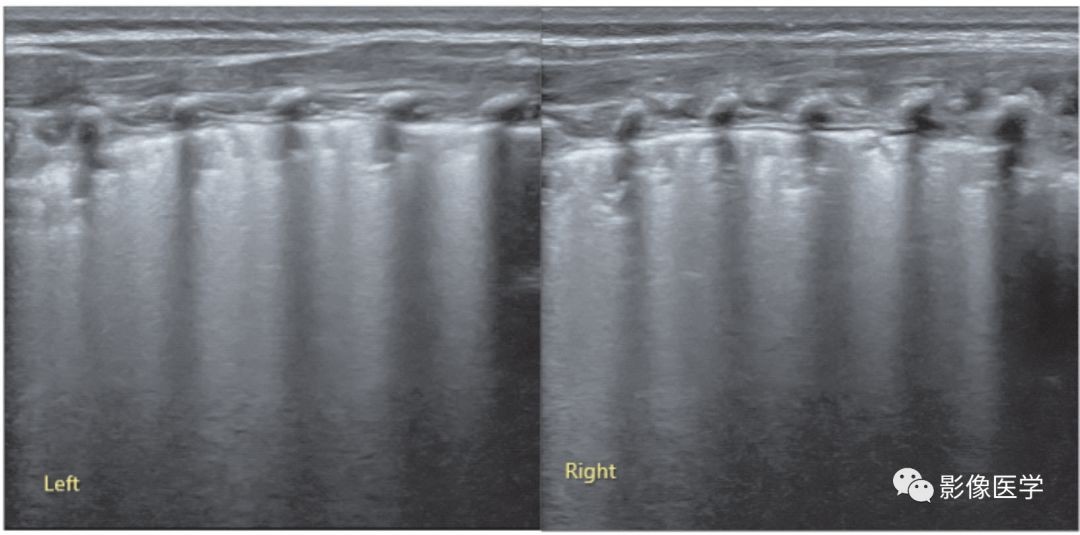

图6-21 感染性肺炎:双肺点

胎龄31周,出生后20d,院内感染性肺炎。肺脏超声显示左肺呈双肺点征象、右肺大面积实变伴支气管充气征。结合上例,说明在肺炎(吸入性或感染性)时也可以见到双肺点,再一次证明双肺点并不是湿肺的特异性征象,任何肺部疾病,当引起上下肺野病变程度不一致或性质不同时,均可以出现双肺点征象。